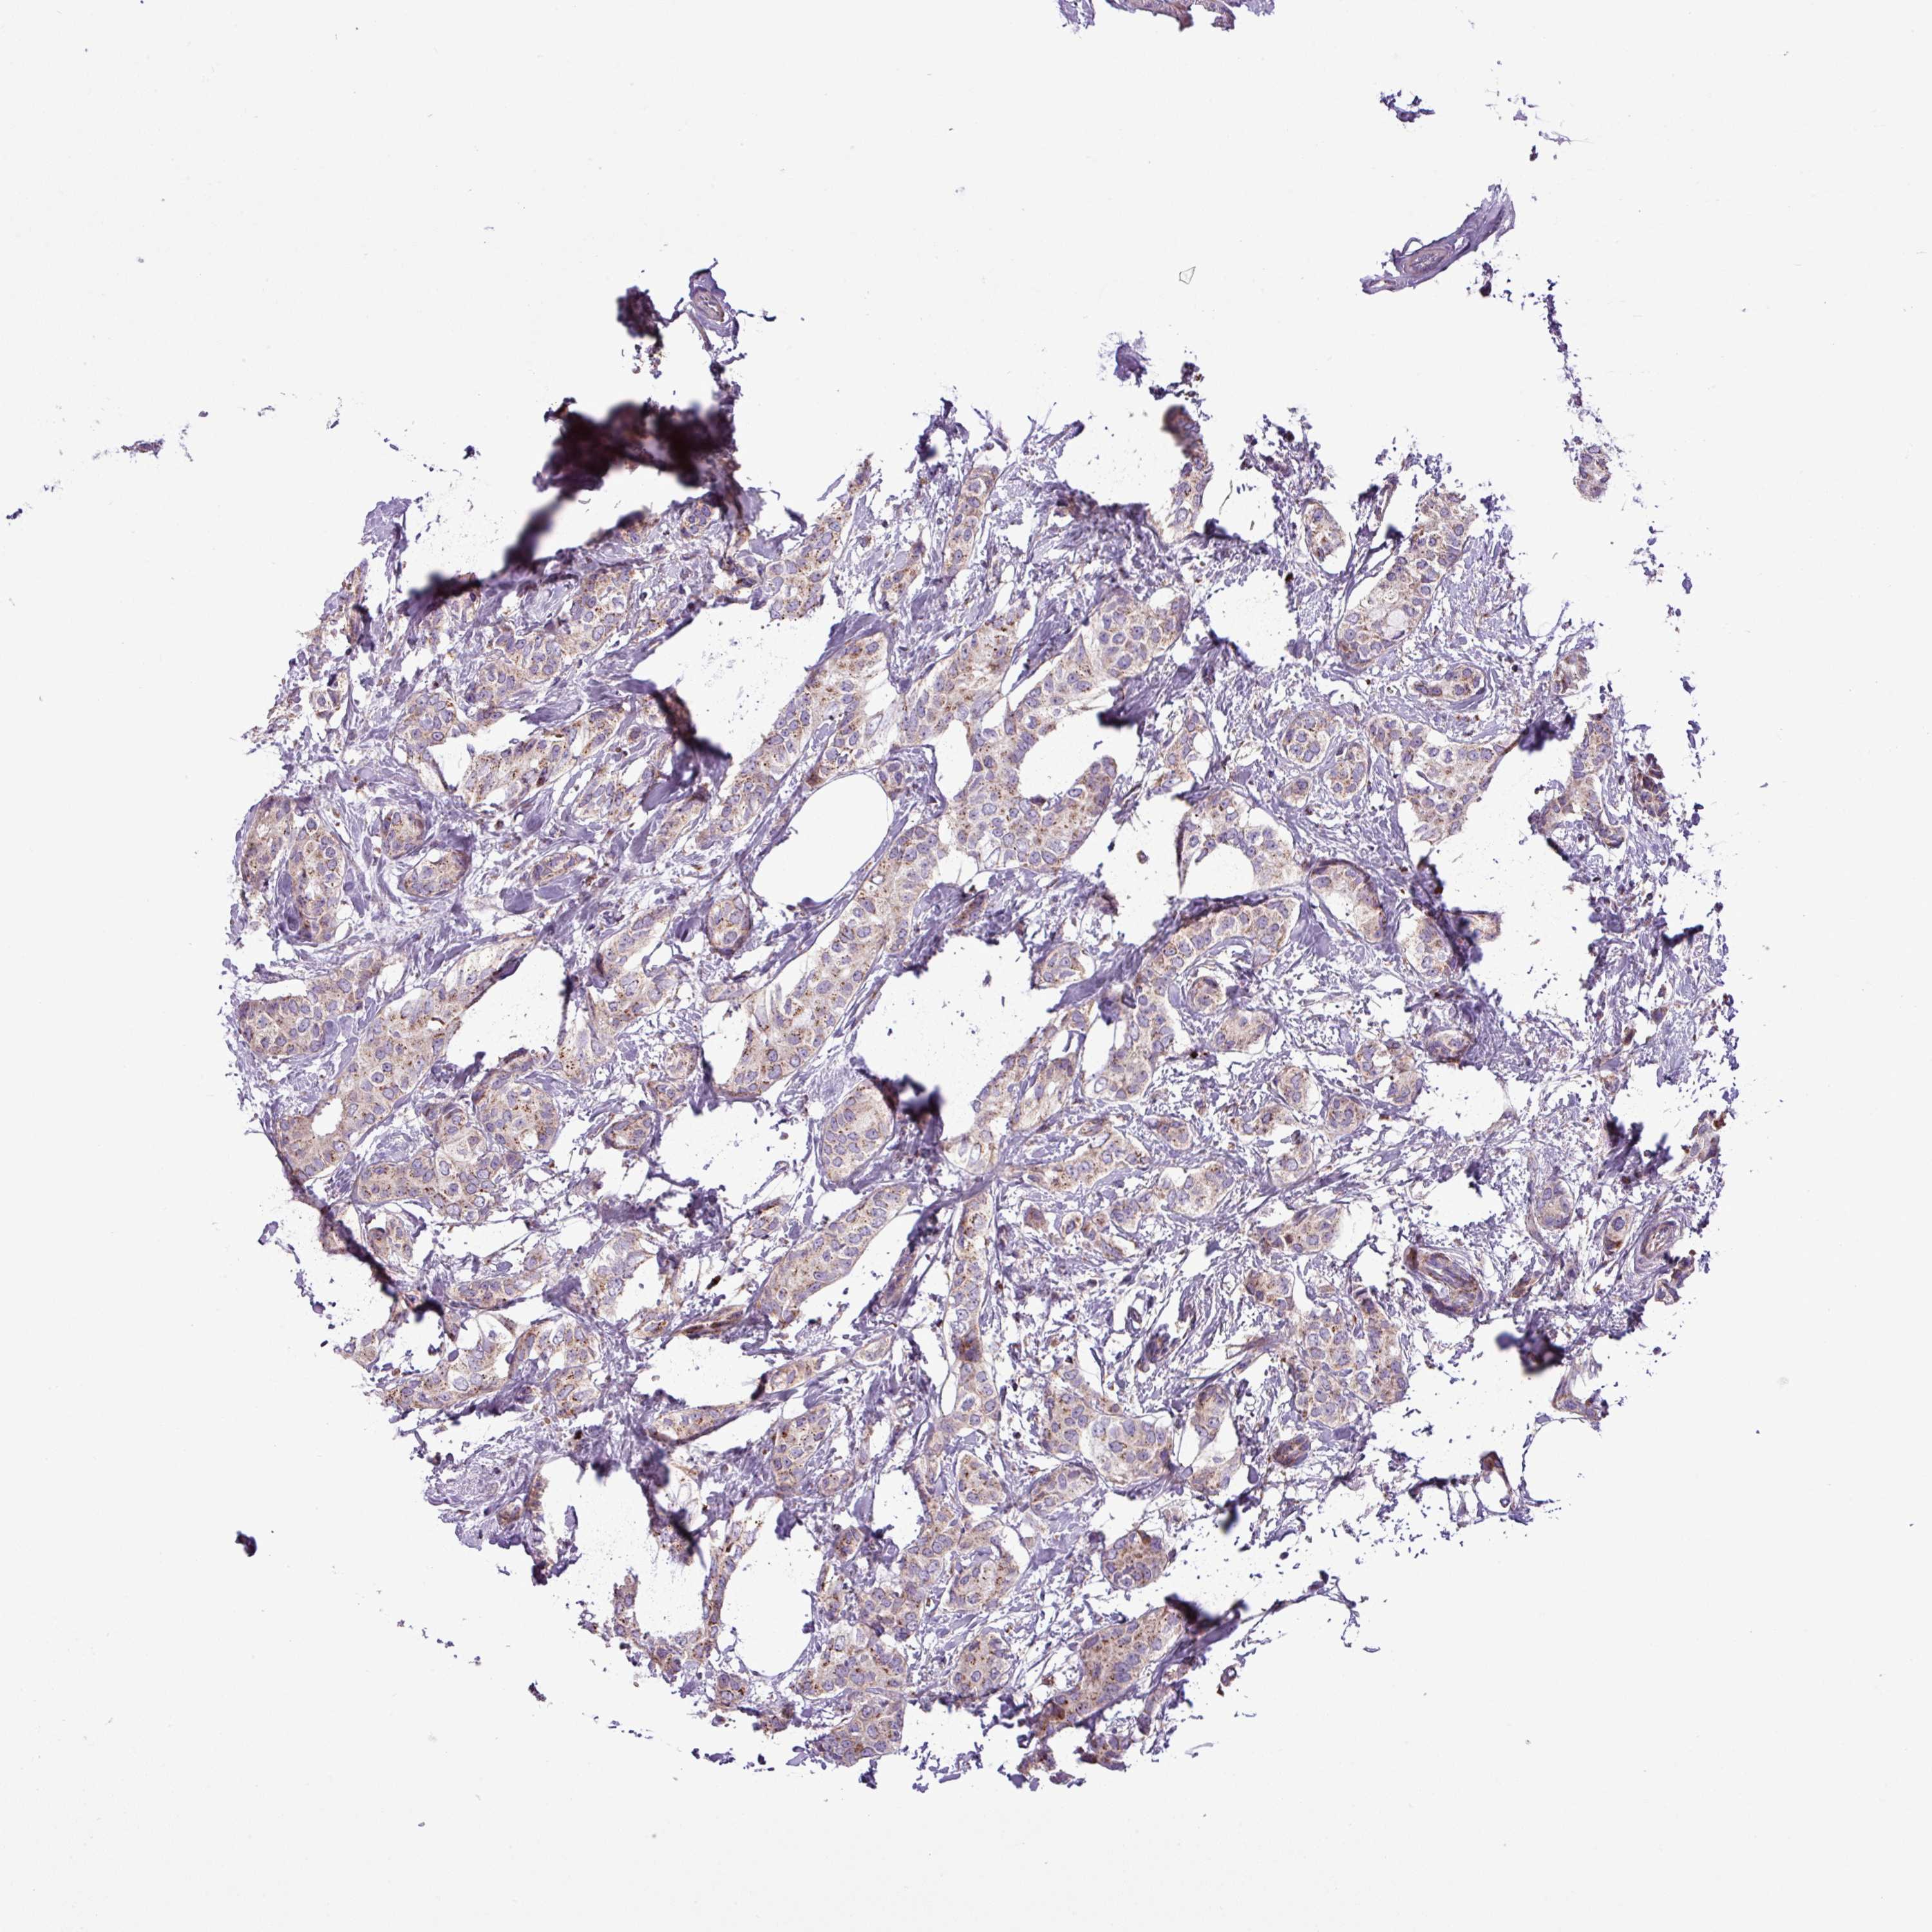

CANCER BREAST CANCER Show tissue menu

BRCA TCGA BRCA VALIDATION PROTEIN EXPRESSION